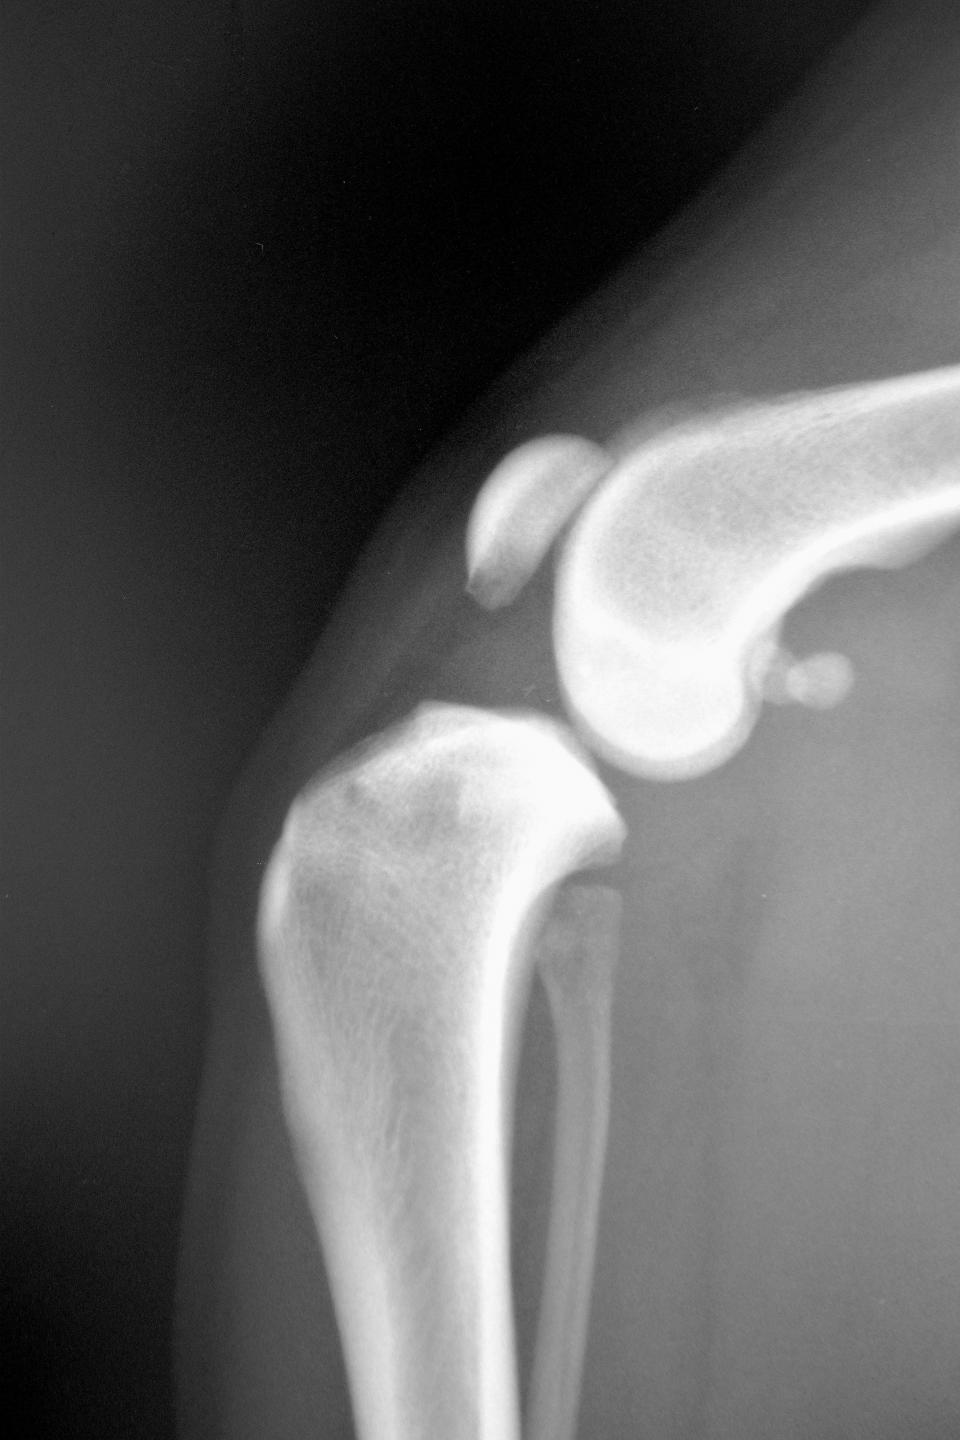

触診検査により患肢の筋肉量低下、膝関節内側面の肥厚(medial buttress)、関節液貯留による関節腫脹などが認められます。脛骨圧迫試験や脛骨前方引き出し試験は前十字靭帯断裂の診断のために古くから行われている検査で、膝関節の不安定性を検出する目的で実施します。脛骨前方引き出し試験では、伸展位と屈曲位のどちらにおいても脛骨の前方変位があれば完全断裂が示唆され、屈曲位のみで前方変位が認められた場合には頭内側帯の部分断裂が示唆されます。しかしながら、部分断裂の約半数は脛骨前方引き出し試験が正常との報告があり、現在ではこれらの所見とともにレントゲン検査でfat pad signや変形性関節症を確認することにより非常に高い精度で診断できます。近年、超音波検査や関節鏡検査、CT検査、MRI検査などが診断ツールとして有用であることが報告されていますが、それぞれに限界点があり、詳細な身体検査やレントゲン検査所見が手術のための診断材料として十分であることがほとんどです。